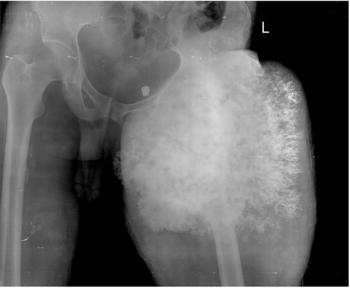

Case History: Skeletal survey for coarse facial features, short stature, spinal deformity in male child of normal intelligence.